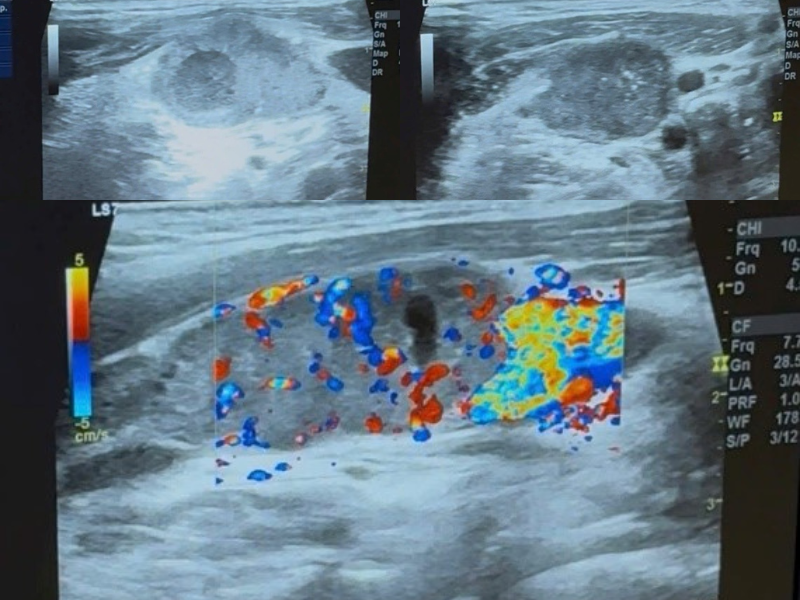

Hình ảnh siêu âm gợi ý ung thư hạ hầu

Siêu âm ghi nhận:

• Khối đặc giảm âm kích thước 27×22mm

• Giới hạn kém rõ

• Xâm nhiễm miệng thực quản

• Tăng sinh mạch máu trên Doppler

• Hạch cổ hai bên mất rốn mỡ, hoại tử trung tâm

Khối u vùng hạ hầu

Hạch di căn

Kết luận siêu âm

Theo dõi K hạ hầu lệch phải, xâm nhiễm miệng thực quản, di căn hạch cổ hai bên.

Điểm đáng chú ý: thực quản bị kéo lệch phải so với khí quản – dấu hiệu xâm lấn ngoài thành.

Siêu âm giúp nhận diện:

• Mất rốn hạch

• Hoại tử trung tâm

• Tăng tưới máu hỗn loạn